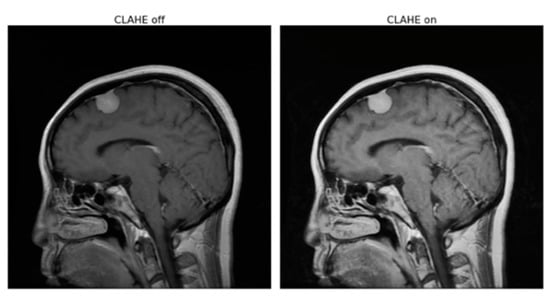

The Contrast Limited Adaptive Histogram Equalization (CLAHE) preprocess has been applied to RGB images by converting the color format from BGR (blue green red) to LAB and then applying CLAHE on the L channel with a custom clip limit and tile grid size. An example of the CLAHE process can be seen in Figure 2.

Figure 2. An example of CLAHE process.